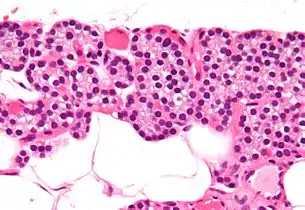

تسمى الغدد جارات الدرقية بهذا الاسم بسبب قربها من الغدة الدرقية - وتقوم بدور مختلف تمامًا عن الغدة الدرقية. يمكن تمييز الغدد جارات الدرقية بسهولة عن الغدة الدرقية حيث أنها تحتوي على خلايا مكتظة بكثافة، على النقيض من البنية الجُريبية للغدة الدرقية.[12] يوجد نوعان فريدان من الخلايا في الغدة الجار درقية:

- الخلايا الرئيسية الدريقية، تصنع وتفرز هرمون جار درقي. هذه الخلايا صغيرة، وتبدو داكنة عند امتلائخا بالهرمون الجار درقي، صافية عند إفراز الهرمون، أو في حالة الراحة.[13]

- الخلايا الحَمِضة الدريقية، أخف في المظهر وتزداد عدديًا مع تقدم العمر،[13] ولها وظيفة غير معروفة.[14]

صورة مجهرية بتكبير متوسط. صبغة الهيماتوكسيلين واليوزين. الأشكال المستديرة البيضاء هي خلايا دهنية. يُشكل النسيج الدهني 25-40 ٪ من نسيج الغدة الدرقية الطبيعي.[13]